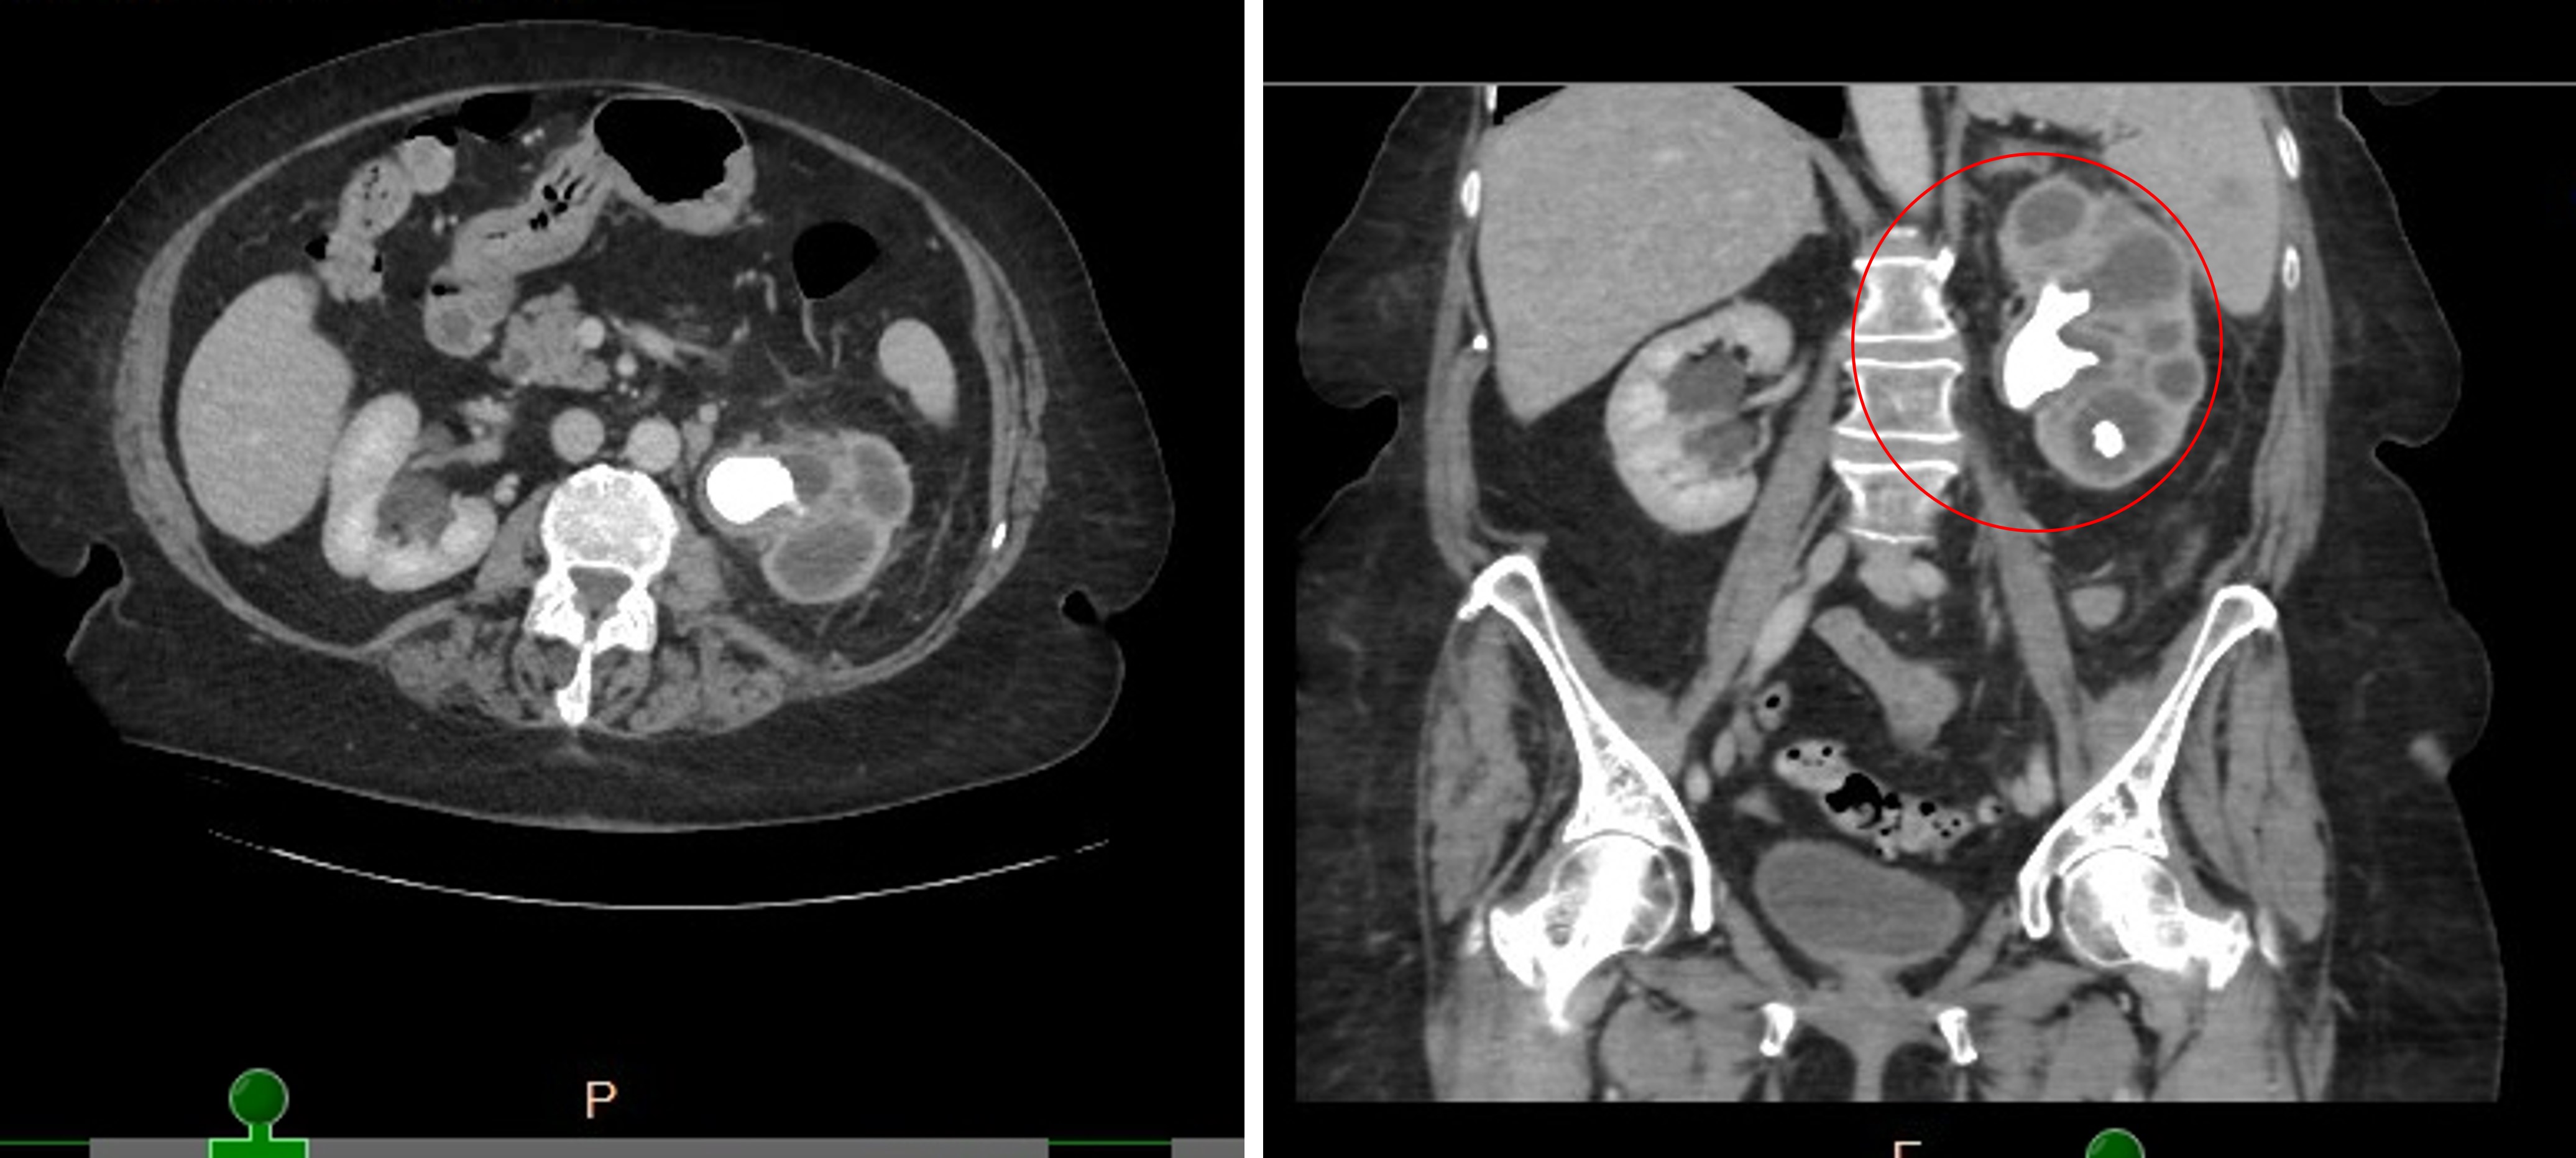

80yr old/ female

History of pyelonephritis, left staghorn calculus, hydronephrosis with left nephrostomy tube placement